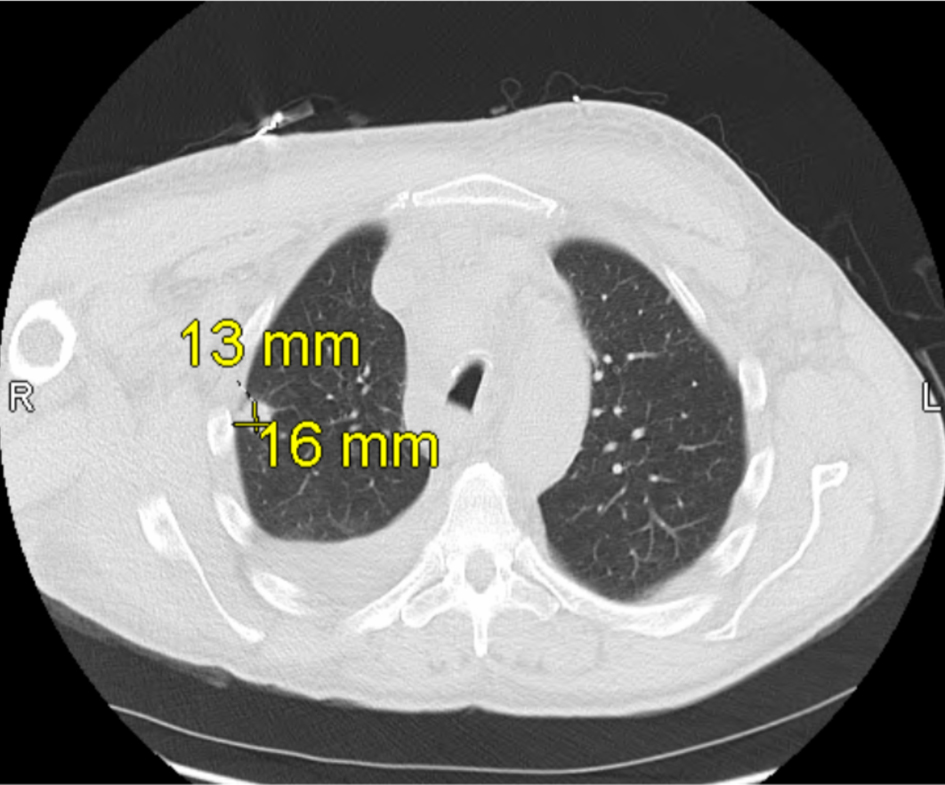

Once admitted, cardiothoracic surgery was consulted and concluded that there were no surgical options for the patient. As the patient’s symptoms progressed, a thoracentesis was performed as well as the initiation of radiation therapy to help reduce the mediastinal mass for suspected SVC syndrome. Additional imaging revealed a 13 × 16 mm mass laterally in the right upper lobe with irregular margins and extension to the pleura laterally (Fig. 2), increase in right pleural effusion, decrease in left pleural effusion, increase in pericardial effusion (Fig. 3), and right upper lobe ground-glass opacities, consistent with pneumonia or atelectasis.

Click for large image

Figure 2. Computed tomography (CT) scan of the chest obtained on hospital day 2 shows a 13 × 16 mm mass in the lateral right upper lobe with irregular margins and extension to the pleura, consistent with findings during early hospitalization for suspected superior vena cava (SVC) syndrome.